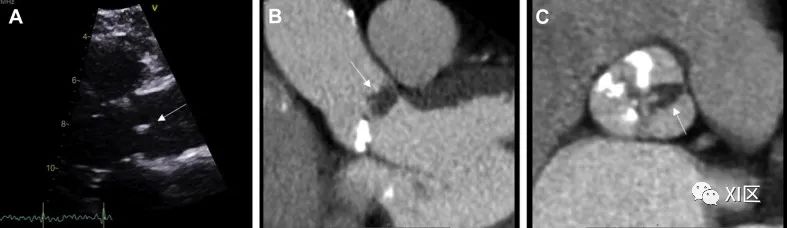

心黏液瘤(图 2)是最常见的 PCT,据信来源于间充质细胞前体。它们形成腔内肿块,最常见于左心房,通过柄与卵圆窝相连,但也可能出现在儿童的右心房。其他解剖学来源包括心房游离壁和二尖瓣瓣叶;但这些来源的可能性较小。有 7% 的患者在就诊时被发现患有心脏黏液瘤,与卡尼综合征(一种多发性肿瘤和皮损综合征)有关联。确诊时的平均年龄为 50 岁,约 70% 的患者为女性。

图 2 黏液瘤53 岁男性,左心房黏液瘤,曾出现栓塞事件。(A)经胸超声心动图检查发现附着在房间隔上的巨大移动肿块(白色箭头)。(B)心脏CT中看到的表面光滑的低衰减、轮廓清晰的肿块(黑箭头)。C)CMR晚期钆成像中左心房肿块的异质摄取(白箭头)。

在超声心动图检查中,心脏黏液瘤通常表现为一个移动的肿块,通过一个柄附着在心内膜表面,通常从卵圆窝产生。RT3DE 可通过裁剪功能和仔细使用数字分析来剖析病灶,从而帮助进行梗阻分析和肿块异质性分析。可能需要进行 TEE 检查,以更好地观察植入部位,并确定是否有可能扩展到肺静脉或腔静脉。在心脏 CT 上,黏液瘤通常表现为腔内低衰减肿块,表面光滑或略带绒毛。约 14% 的患者可见钙化,右侧病变更常见。动脉期造影剂强化通常不存在,但在较长的时间延迟下进行的检查中可发现异质强化。电影图像的重建有助于评估病变的移动性和附着情况;但这往往并不可靠,尤其是对于茎干较短的肿瘤。在 CMR 上,T1 和 T2 加权图像上通常会出现异质外观,这是由于黏液瘤的成分所致,黏液瘤往往含有不同数量的黏液组织、出血组织、骨化组织和坏死组织。延迟强化通常是斑片状的。在稳态自由进动序列上,二尖瓣或三尖瓣在舒张期脱垂可能提示有蒂病变的附着点。